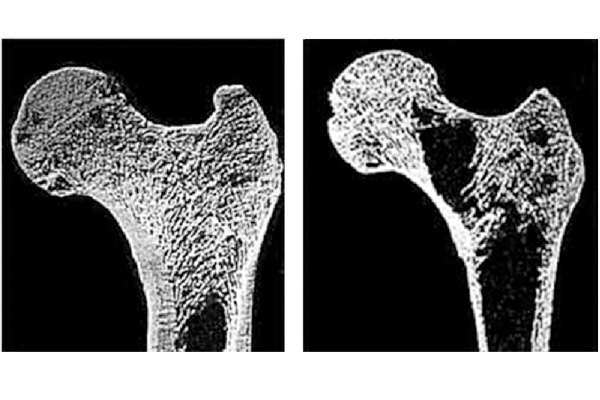

O osso é uma estrutura viva que precisa se manter saudável. A osteoporose ocorre quando o corpo deixa de formar material ósseo novo suficiente, ou quando muito material dos ossos antigos é reabsorvido pelo corpo – em alguns casos raros, podem ocorrer ambas as coisas. Se os ossos não estão se renovando como deveriam, ficam cada vez mais fracos e finos, estando sujeitos a fraturas, principalmente nas vértebras.

Para diagnosticar a doença, é necessária a realização de uma densitometria óssea, que consiste num exame onde averígua-se se o paciente possui perda de massa óssea. A densitometria é realizada com o paciente deitado sobre uma maca, imóvel, até que um aparelho registre imagens radiológicas de seu corpo. O exame dura, em média, 10 minutos e é indolor. A principal causa da osteoporose é a diminuição da densidade óssea decorrente do processo natural de envelhecimento. Porém, existem também outras causas, tais como uso abusivo de cigarro e álcool, quedas frequentes e pouca atividade física.